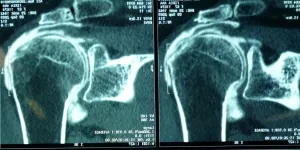

Bilan préopératoire ou Comment faire le diagnostic

L’examen clinique complet du patient par votre médecin permet d’évoquer le diagnostic (douleurs d’épaule nocturnes…), d’éliminer des lésions associées (fracture, capsulite rétractile,…) et de proposer un bilan complémentaire adapté (radiographie, échographie, arthro-scanner, IRM, arthro-IRM, électromyogramme).

Lorsqu’il existe une rupture de la coiffe des rotateurs, l’étendue des lésions dans le plan frontal (distale, intermédiaire ou rétractée à la glène), dans le plan sagittal (rupture complète ou incomplète, nombre de tendon atteint ; si ≥ 2 tendons = rupture massive), en épaisseur (rupture transfixiante ou partielle ; face profonde ou superficielle) doit être décrite de manière précise.

Par ailleurs, le bilan apprécie la qualité osseuse (ostéoporose, lacune osseuse) et musculaire (infiltration graisseuse).